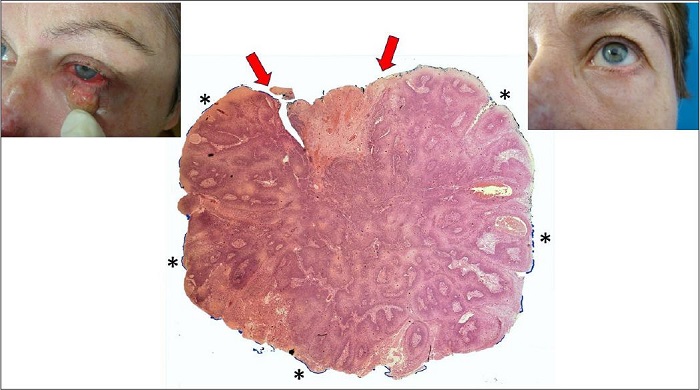

Alguns patologistas usam o termo “margens coincidentes” quando o tumor aparenta apenas tocar focalmente a borda cirúrgica. Outros preferem julgar esta situação como margem comprometida ou focalmente comprometida. Sem dúvida, isso pode representar um dilema quando, na realidade, o tumor apenas tangencia a borda cirúrgica, mas não a ultrapassa. Quando se examinam casos como esses, sem dúvida a interpretação do patologista como margem comprometida está correta, mas nunca vi um patologista escrever em um laudo que pode tratar-se de um falso-positivo. Uma das características da borda tumoral nestas circunstâncias é seu aspecto arredondado ou curvo. Bordas tumorais retas coincidindo com borda cirúrgica devem ser interpretadas realmente como verdadeiras margens comprometidas (Figura 7). Em alguns casos, pela arquitetura da lesão, é mais fácil imaginar que esta borda seja apenas coincidente (ex: carcinoma basocelular nitidamente nodular). Porém, em casos micronodulares, infiltrativos ou com blocos pequenos, pode ser difícil afirmar que a margem é apenas coincidente, afastando-se a possibilidade de ter restado blocos residuais no leito cirúrgico no paciente. Por isso, o subtipo histológico e o padrão arquitetural do tumor devem ser muito valorizados na interpretação.

MARGENS COMPROMETIDAS

A margem está comprometida quando a borda cirúrgica, que deve estar pintada, coincide com a borda tumoral que se apresenta geralmente reta (isto é, dando a impressão de ter sido seccionada). Outras vezes, o tumor é bastante infiltrativo, de forma que projeções digitiformes dele aparecem seccionadas na borda cirúrgica. Muitos patologistas não mencionam a quantidade de tumor nos cortes que tocam as bordas cirúrgicas, desta forma não distinguindo até um possível caso de margem coincidente focal como acima descrito, de um caso no qual uma grande quantidade de tecido tumoral acomete a borda cirúrgica. O cirurgião atento para esta situação pode se sentir mais seguro com sua conduta de reoperar se perceber que grande quantidade de tecido tumoral tocava a borda cirúrgica (Figura 8).